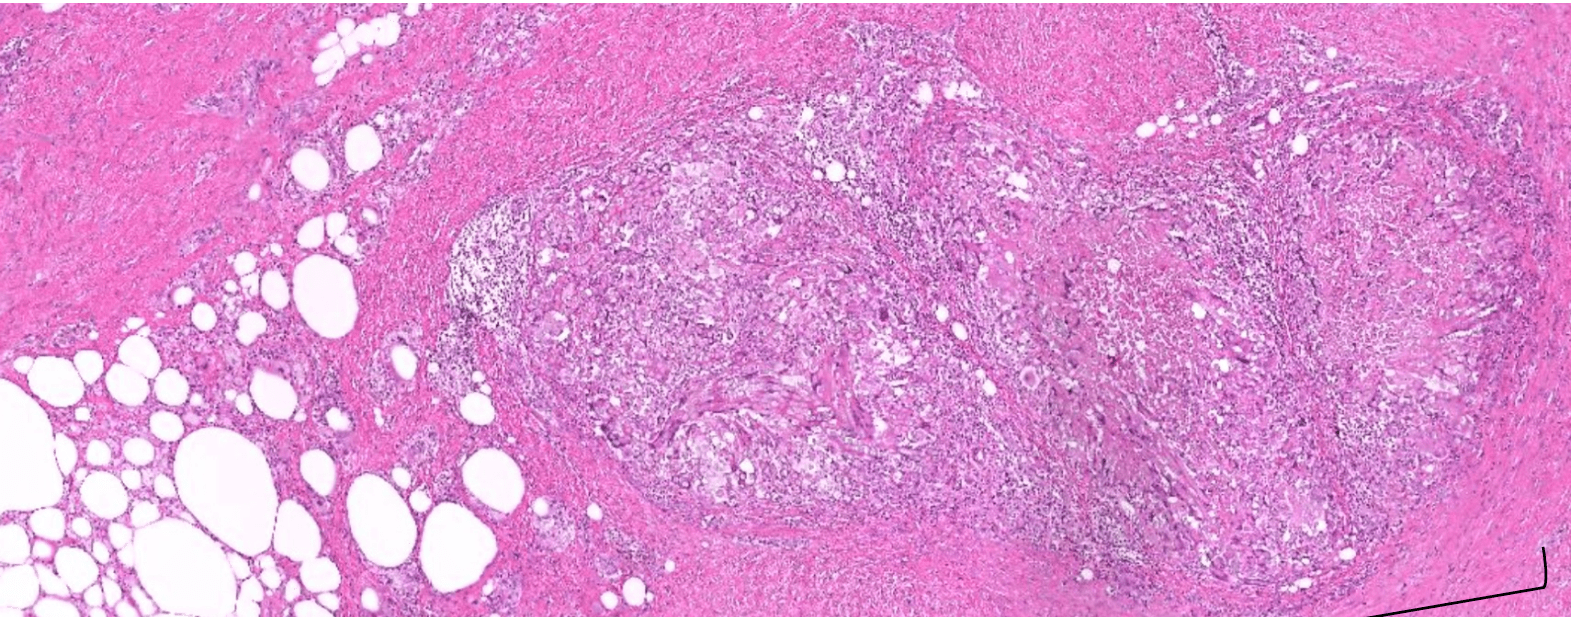

lung adenocarcinoma

colon cancer

endometrial cancer